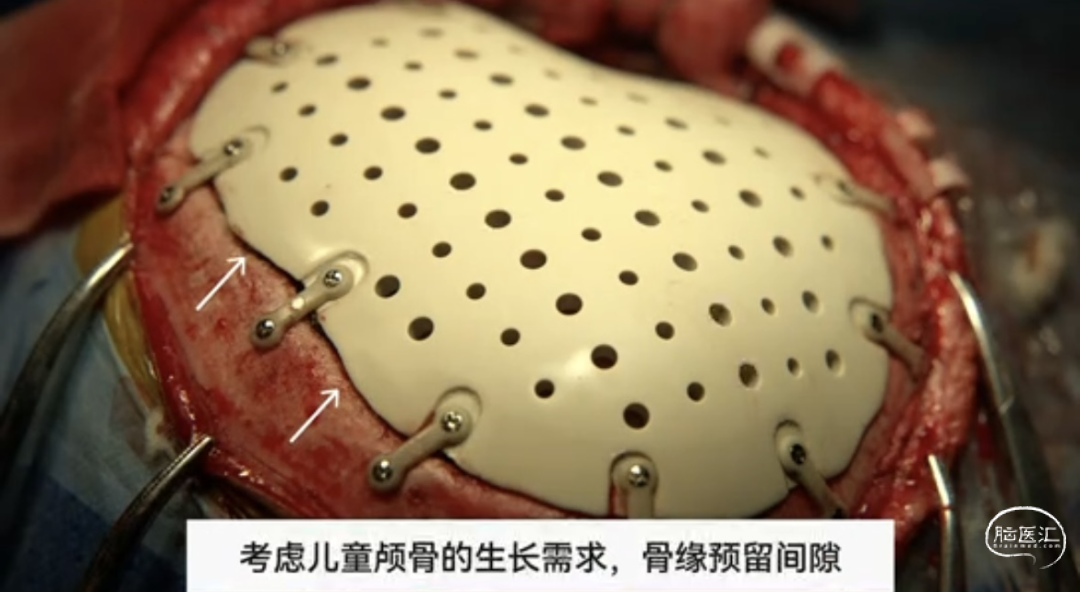

① 7岁儿童,要兼顾颅骨发育可能➡定制修补材料需与骨窗缘预留1~2mm间隙

步骤三:安装PEEK颅骨,用PEEK连接片将假体颅骨固定在骨窗,并缝合骨膜和颞肌瓣